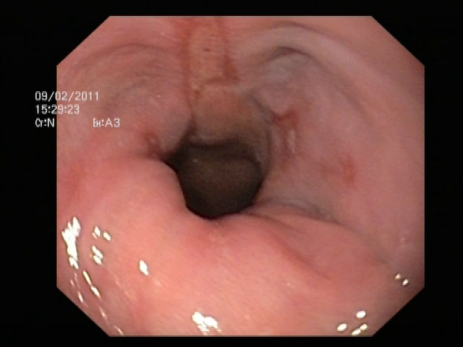

- Endoscopia digestiva alta (o esofago-gastroscopia)

: Permite confirmar la presencia de una hernia de hiato y en caso de que exista reflujo gastroesofágico evidenciar la presencia de esofagitis si la hubiera. Permite tomar biopsias para descartar lesiones premalignas en el esófago de Barret.